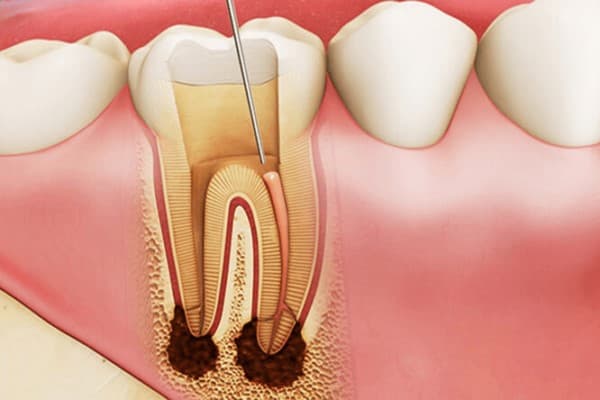

Tủy răng, một phần quan trọng của răng, bao gồm nhiều mô và dây thần kinh, có vai trò quan trọng trong việc dẫn truyền cảm giác và cung cấp chất dinh dưỡng cho răng. Tủy răng vốn rất nhạy cảm ngay cả với những tác động nhỏ nhất. Khi răng bị viêm nhiễm mà tủy vẫn còn, thường được đề xuất sử dụng thuốc diệt tủy răng trước khi thực hiện điều trị. Mục tiêu của việc này là giảm triệu chứng đau đớn cho bệnh nhân trong và sau quá trình điều trị.

– Tiêu diệt triệt để tủy răng đã hỏng : Thuốc điều trị tủy răng hoạt động trên cơ chế loại bỏ tủy răng nhưng không làm cho cấu trúc xương cũng như mô mềm xung quanh bị thương tổn.

– Hiệu quả cao : Sau khi sử dụng thuốc diệt tủy răng, vi khuẩn gây tổn thương tủy răng sẽ bị tiêu diệt một cách hiệu quả, ngăn ngừa vi khuẩn phát triển và lây lan sang các vùng xương hàm khác.